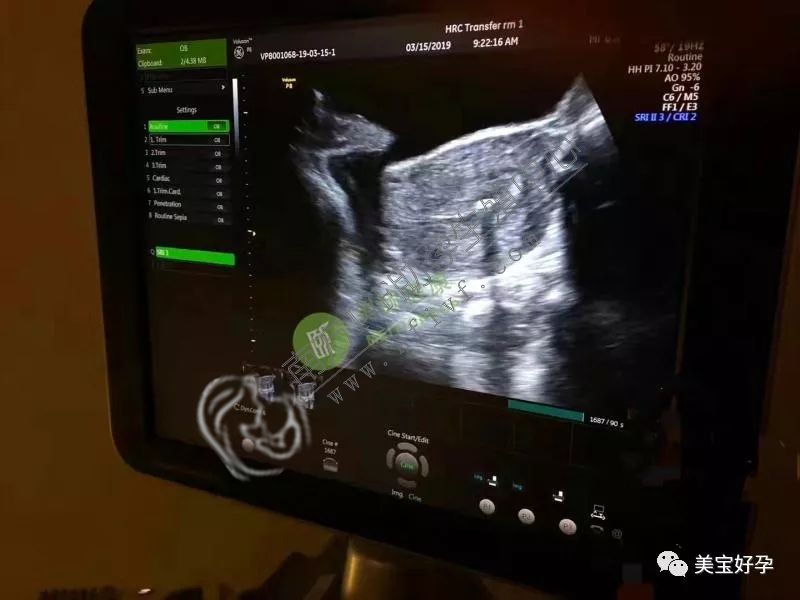

周二,为苏州张氏夫妇助孕的爱心妈咪来到诊所进行了移植手术,这是一位漂亮的美女姐,从答应帮助张先生一家做第三方辅助助孕以来她一直很兴奋,这是她第一次帮助别人,一种神圣的孕产使命感驱动着她用非常认真的心态对待此次移植手术。

虽然整个过程仅有短短的五分钟,但她已经为此调理了很长一段时间的身体,要以最好的状态来迎接这个小天使的到来。

这周三,为他们助孕的妈咪穿着简单的衣着就来到诊所,移植后还和我们工作人员及远在南京的陈夫妇进行了视频通话,一切都显得顺利自然。

周五,又是一位爱心妈咪顺利完成移植的孕产日子,原本前两个月就该完成的移植手术,因为求助的青岛夫妇的原因断断续续耽搁了一段时间,直到现在才实施,不过我们的助孕麻麻超有耐心,一直在安心等待通知。终于顺利移植啦,听到这个好消息,国内的准父母也是非常的欣喜开心。